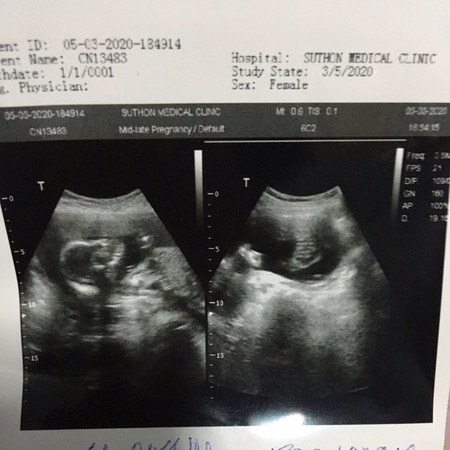

เพศลูก

ลุงหมอบอกว่าหนูอาจจะเป็นผู้หญิง เพราะไม่มีจู๋โผล่ออกมา สมใจพ่อกับแม่เลยค่ะ แต่ก็ต้องลุ้นเดือนต่อไปว่าจะโผล่ไหม? คุณแม่ทีม กค.ได้ลูกสาวหรือลูกชายกันค่ะ เอารูปมาแลกเปลี่ยนกันหน่อยจ้า ?❤️

หมอบอกผู้หญิงเหมือนกันคะ แต่กลัวมีจู๋โผล่ออกมาจัง 😂😂

หมอบอกผู้หญิง80%จ้า